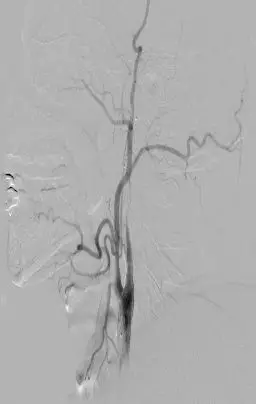

颈内动脉DSA提示颅内存在三处病变血管:大脑中动脉上干闭塞,下干的起始段局部有血栓形成以及一支M2段分支闭塞。

下干取栓后DSA可见下干开通,M2分支以及大脑中动脉上干部分开通。

使用4-20 Solitaire 支架进行MCA上干取栓。 取栓后DSA提示上干完全再通,M2远端分支仍闭塞。

使用4-20 Solitaire 支架进行M2远端分支取栓。 取栓后DSA提示三支病变血管均完全开通。